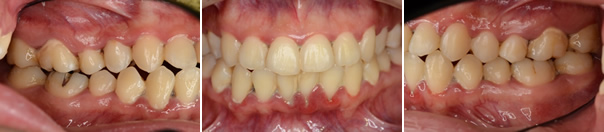

抗菌剤(メトロニタゾール)の投与とクロルヘキシジン溶液の洗口をおこない、栄養指導、禁煙指導も行いました。症状が軽減した後、通常の基本治療を行いました。

・メインテナンス時